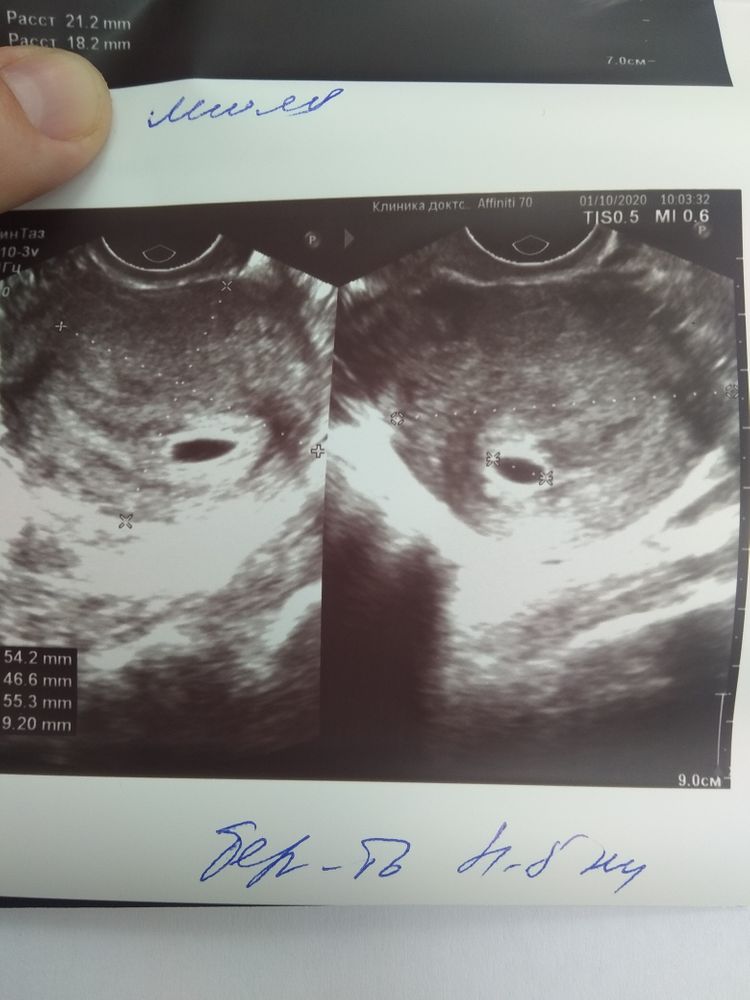

ФолликулометрияОх девочки😁,неделя переживаний,пошла сегодня на УЗИ,срок 4-5 недель!!!( По месячным календарики выдает ровно 6 недель).

В матке плодное яйцо диаметром 9.2 мм,жёлтое тело ( левый яичник) 20 мм.